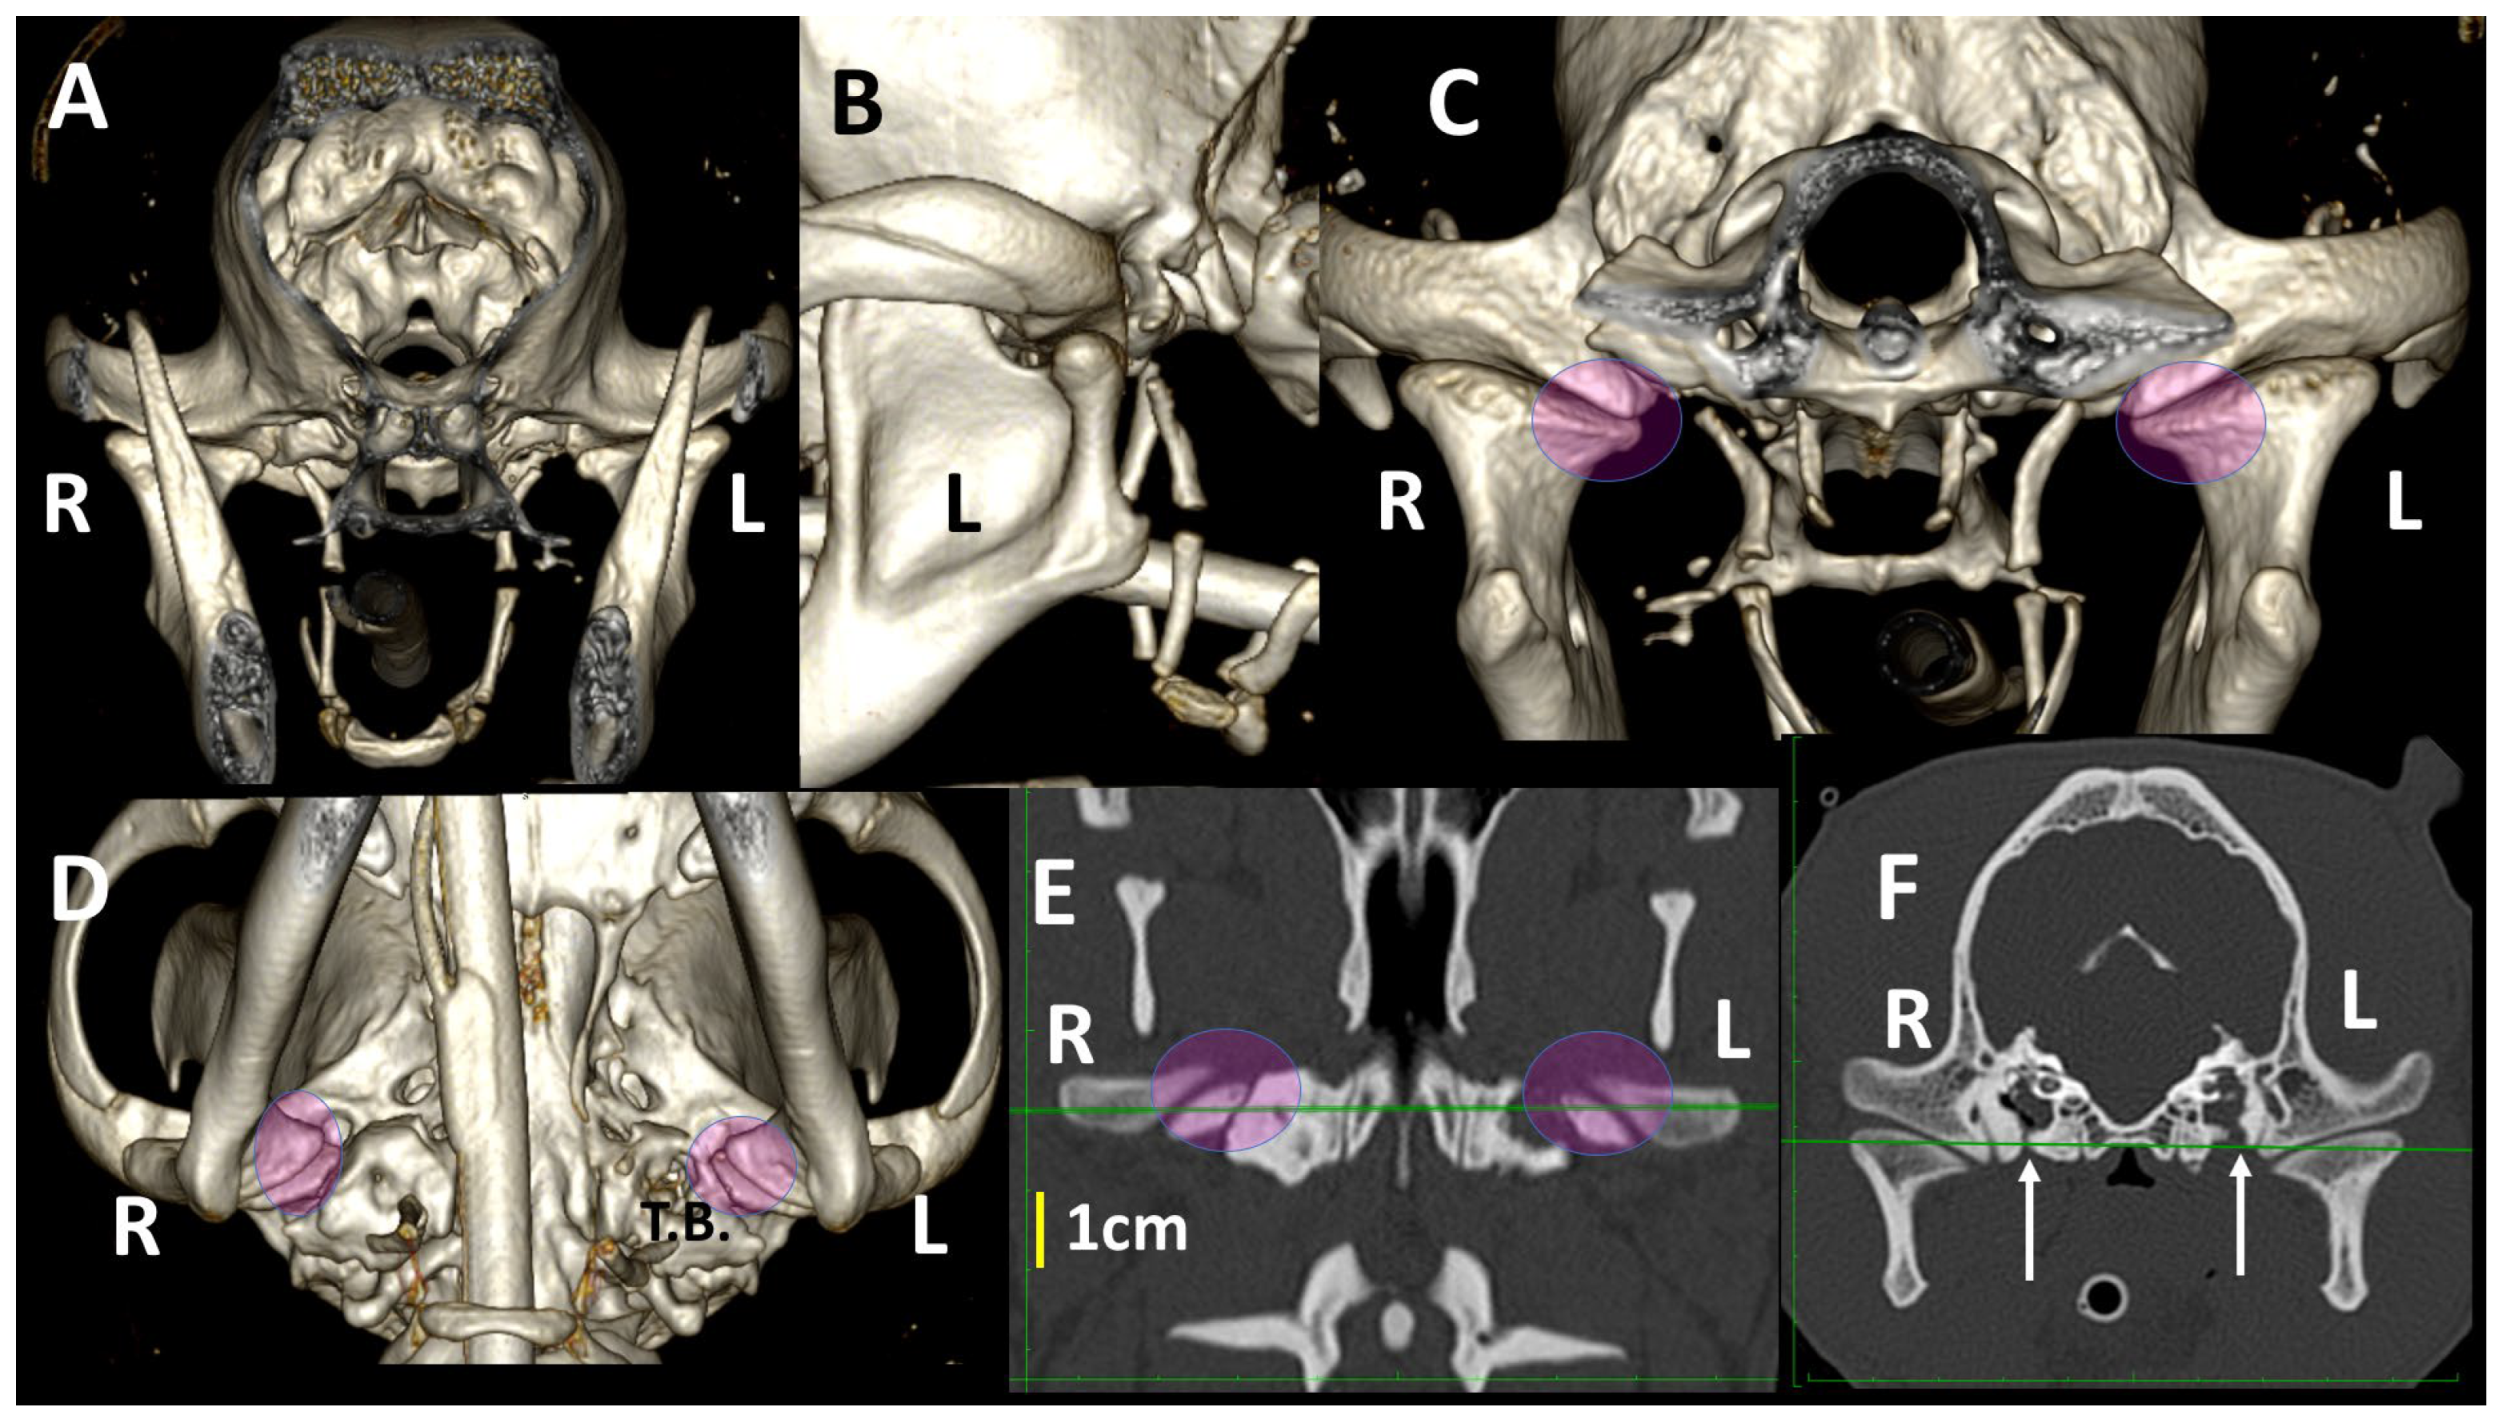

3.1. A Detailed Description of the Bone Anatomy of TMJ Using 3DVR Images

3.2. Comparison by 3DVR of TMJs in Each Dog, According to Skull Type and Age